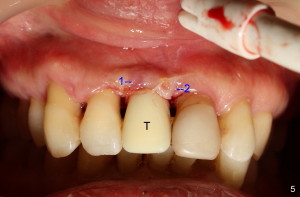

Fig.4 shows incision design for implant uncover (following osseous surgery in the upper right quadrant). The main incision is indicated by black line, lingual to the crest so that the buccal flap is more bulky. It is curved and festooned to create the future cosmetic buccal gingival margin. If the main incision is placed too lingual to expose the implant, one or two accessory incisions (red) can be made. After insertion of 4x6.5 mm non-shouldered abutment 3 mm post, PVS impression is taken. Fig.5 shows temporary crown in place (T) with two vertical mattress suture in the mesial and distal papillae. Two accessory incisions are approximated. Two weeks later, the temporary crown is removed. The accessory incision #1 has healed, while #2 is healing (Fig.6). The temporary crown helps form a nice socket around the abutment (A). Fig.7 shows the gingiva around the crown (to be cemented) with healing incision #2. Five months after crown cementation, the gingiva looks healthy.